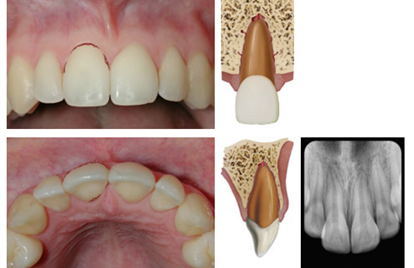

81

root fracture dx

coronal segment may be mobile and in some cases displaced. Transient crown discoloration (red or grey) may occur. Bleeding from the gingival sulcus may be noted. May be TTP May be mobile Sensibility testing may give negative results initially, indicating transient or permanent neural damage. Monitoring the status of the pulp is recommended. * The pulp sensibility test is usually negative for root fractures except for teeth with minor displacements. The test is important in assessing risk of healing complications. A positive sensibility test at the initial examination indicates a significantly reduced risk of later pulp necrosis. Periapical, occlusal and 2 eccentric exposures. * An occlusal exposure is optimal for locating root fractures in the apical and middle third. Bisecting angle exposure or 90 degree angulation exposure is needed to locate the fractures in the cervical third of the root. * In cases where the above radiographs provide insufficient information for treatment planning, CBCT can be considered to determine the location, extent and direction of the fracture. root fracture line is usually visible. The fracture involves the root of the tooth and is in a horizontal or diagonal plane